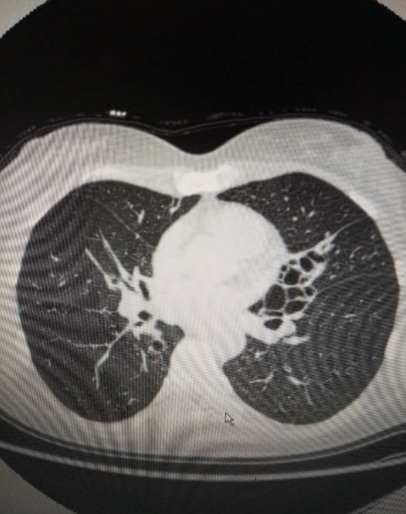

4、干性支气管扩张的唯一症状是反复咯血支气管扩张是由于支气管及其周围肺组织发生慢性化脓性炎症和纤维化,导致支气管壁的肌肉和弹性组织受到破坏,进而引发支气管变形及持久扩张其典型症状包括慢性咳嗽咳大量脓痰以及反复咯血然而,在部分患者中,反复咯血可能成为唯一的症状,这种情况在临床上被称为干性。

5、咯血对人体的危害咯血容易堵塞支气管和气管,导致支气管闭塞,严重时可能产生窒息现象支气管堵塞还可能引起肺不张,进一步影响呼吸功能生命危险的潜在性窒息可引起呼吸暂停,对患者的生命安全构成严重威胁因此,一旦出现咯血症状,需要立即就医进行治疗,以防止病情恶化综上所述,支气管扩张吐血是一;2 反复咯血约50%~70%的患者会出现咯血,程度从痰中带血丝到大咯血不等咯血是支气管扩张的典型特征之一,与气道黏膜血管破裂相关3 反复肺部感染由于气道结构破坏和抵抗力下降,患者易因细菌定植引发反复肺部感染,表现为咳嗽加重痰量增多发热等症状4 慢性感染中毒症状长期感染可导致全身性。